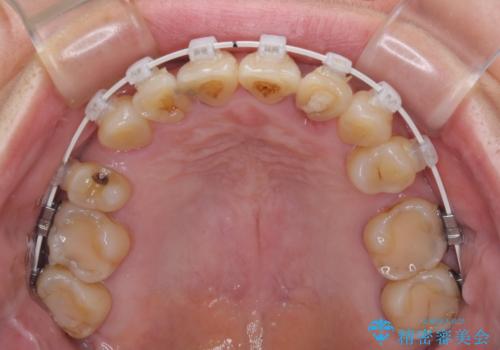

- 矯正装置

- 審美装置

前歯のデコボコおよび奥歯の咬み合わせを改善するために、上顎左右の小臼歯を欠損スペースを利用して歯列を整え、矯正治療後に気になる上下前歯などをオールセラミッククラウンで美しく仕上げていくこととしました。